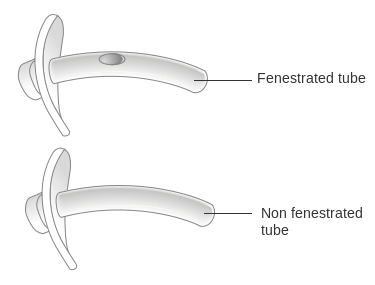

- Invasive Mechanical Ventilation – here a tracheostomy (insertion of a tube into the trachea from outside) is performed. It is only applied when the rest of the measures have failed (i.e., CPAP or NIV fails; deteriorating blood gases despite focused medical treatments) or conditions such as, clinical deterioration, sever respiratory acidosis or muscle fatigue. There are very high risks and complications of invasive mechanical ventilation and therefore it is only commenced in special cases and alway by a intensivist/specialist.